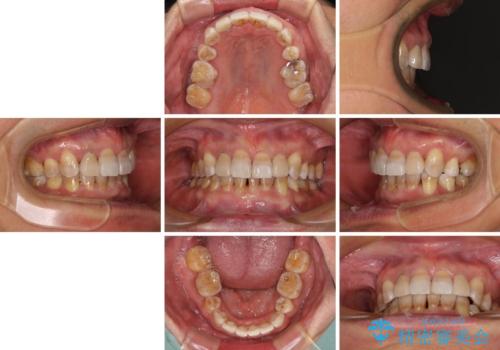

小臼歯の抜歯する部位を選択したことで、安定した咬み合わせとなりましたが、第二小臼歯を抜歯した部分はスペースを閉じるのに長い期間を要しました。

矮小歯であった上顎前歯2本は、矯正治療後にバランスの取れた大きさのオールセラミッククラウンを装着しました。